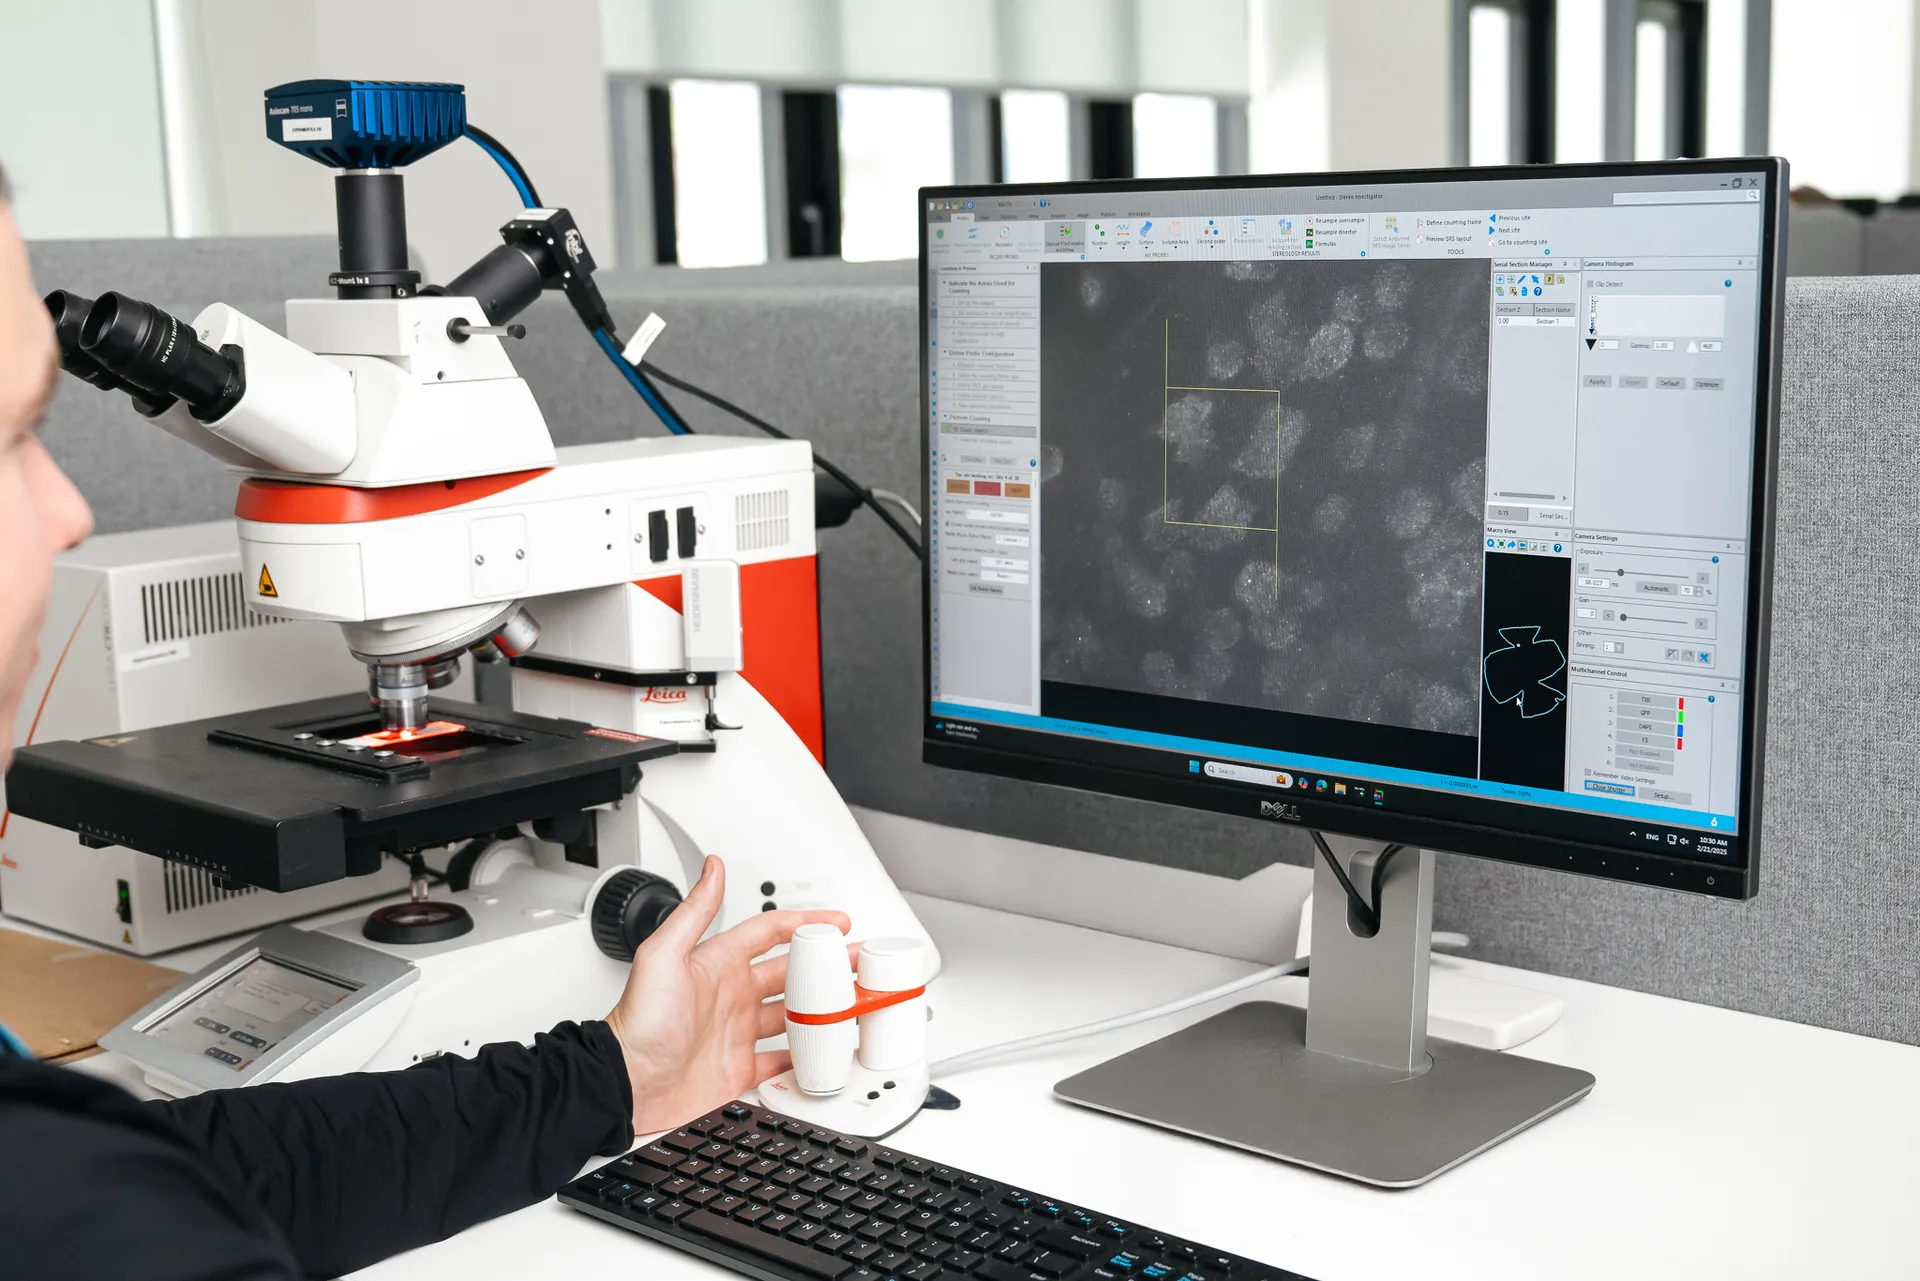

– Quantitative analysis of retinal ganglion cells loss

AI-driven analysis of retinal thickness measurements and retinal ganglion cell estimation using stereology ensures unbiased evaluations of neuroprotective treatments